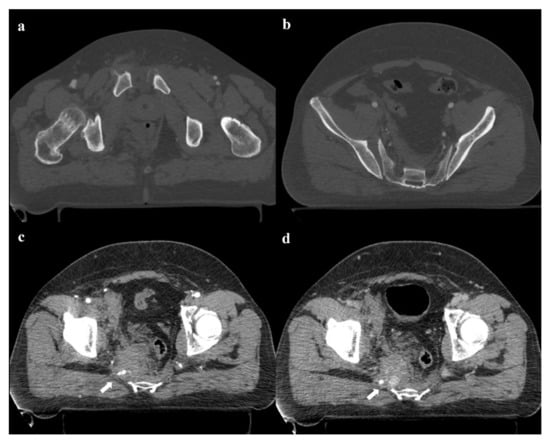

Plain radiography is also important in the follow-up of pelvic fractures, by performing anteroposterior and oblique outlet and inlet projections (Figure 9). The outlet view is obtained by directing the inclination of the x-ray beam tilt from the feet at an angle of 35° to the x-ray table, and it allows detection of sacral fractures and craniocaudal dislocations. The inlet view is obtained by directing the inclination of the X-ray beam tilt from the head at an angle of 35° to the X-ray table, and it allows detection of any anteroposterior displacement of the sacroiliac joint or any rotation of a hemipelvis [17,36].

Figure 9. Plain radiography. The outlet view (a) and the inlet view (b) show a 5.2 cm diastasis of the pubic symphysis and anterior widening of the left-side sacroiliac joint. These findings have to be quickly reported to allow prompt treatment.